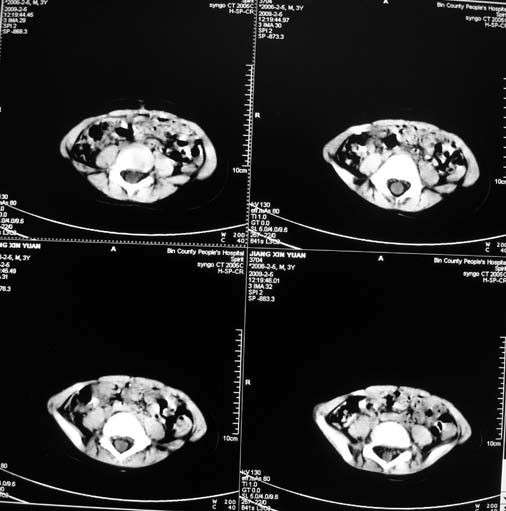

男,3岁,肾母细胞瘤术后,肝脏的低密度是什么?

胰尾下方见两枚囊形灶,肠管?病灶?左侧肾上腺区见团块状影,转移病灶?术后表现?建议与前片对比,肝脏病灶好像有牛眼表现,不除外转移,如果不增强,建议加做个b超,至少可分清其囊性或者实性,又便宜,免费自已给他弄一下也行,对诊断有帮助

左肾母细胞瘤术后,多发性转移可能性大。

左肾母细胞瘤术后:肝脏多发低密度灶,考虑转移可能性大。

左肾母细胞瘤术后:肝脏多发低密度灶,考虑转移可能.请结合临床及增强以及术前检查等